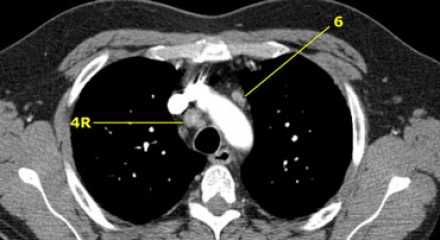

4R. Правые нижние паратрахеальные лимфатические узлы

- Верхняя граница: пересечение нижнего края левой плечеголовной вены с трахеей.

- Нижняя граница: нижний края непарной вены. 4R узлы распространяются до левого края трахеи.

На изображении слева мы видим 4R паратрахеальные узлы. Кроме того здесь представлен узел кнаружи от дуги аорты, то есть 6 группы.

4L. Левые нижние паратрахеальные лимфатические узлы

4L узлы расположенные слева от левой стенки трахеи, между горизонтальными линиями проведенными касательно верхней стенке дуги аорты и линией проходящей через левый главный бронх на уровне верхнего края верхнедолевого бронха. Они включают паратрахеальные узлы расположенные кнутри от артериальной связки.

Узлы 5 группы (аортопульмонального окна) расположены кнаружи от артериальной связки.